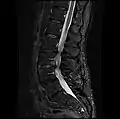

MRI lumbar spine with degeneration, post-hemilaminectomy L4-5 (sagittal T2 FRFSE)

MRI lumbar spine with degeneration, post-hemilaminectomy L4-5 (sagittal T1 FSE)

MRI lumbar spine with degeneration, post-hemilaminectomy L4-5 (sagittal FAST STIR)- MRI lumbar spine post-hemilaminectomy (sagittal T2 FRFSE)